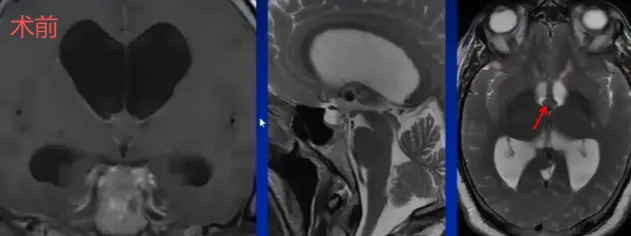

一例脑胶样囊肿患者伴有脑积水、行走障碍和记忆力减退等症状,病情危急,进展迅速。Schroeder教授在导航引导下,使用LOTTA脑室镜配合鞘管穿刺针进入侧脑室额角,成功全切第三脑室胶样囊肿。术后3年随访显示无复发征象。

术前影像可见明显病变占位,术后复查确认病变完全切除,手术效果显著。